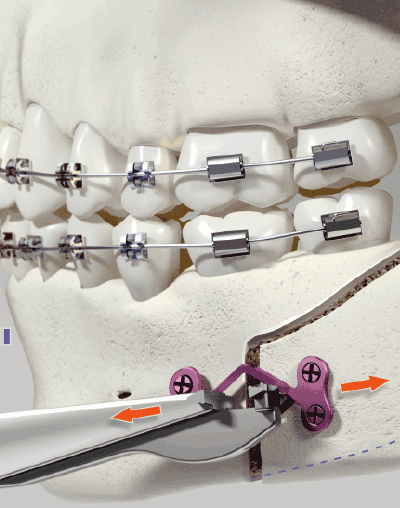

ORTRAUTEK est une gamme complète, dédiée à la chirurgie orthognathique, génioplastie, traumatologie et petite reconstruction.

Il s’agit d’un très large panel de vis et de plaques de différentes formes se déclinant dans des épaisseurs et des grades de titane distincts, le tout aisément identifiable grâce à un code couleur.